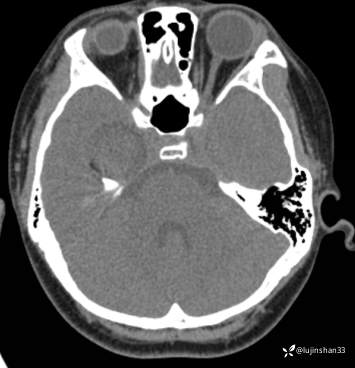

术后

【临床诊断】:颅底占位

【治疗经过及结果】:显微镜下颅中窝入路右侧颅底病变切除术,术后恢复良好。